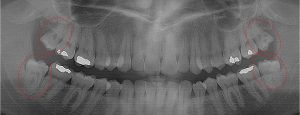

This 19 year old patient has all four 3rd molars present (circled). The roots are +90% formed. Both lower 3rd molars are impacted against the 2nd molars with no chance of further eruption and a +60% probability of decaying before age 30. The patient presented with pain and infection around both lower 3rd molars, requiring immediate extraction